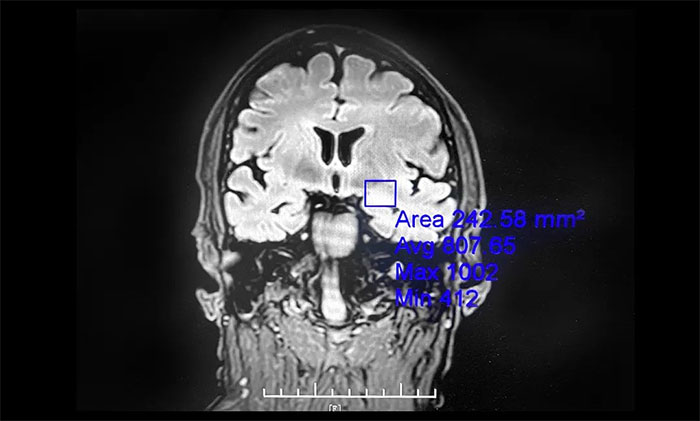

▲ 癫痫外科手术为癫痫患者带来希望